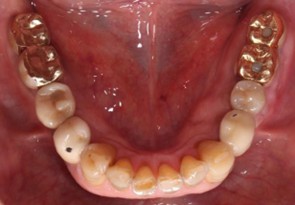

60代 男性

治療前

治療後

治療後- 年齢/性別

- 60代/男性

- 主訴

- 右上7~5/左下6・7

- 治療期間

- 12ヶ月

- 治療費

- インプラント¥1,760,000

骨造成¥220,000

サージカルステント¥110,000 - リスク・副作用

- 術後の腫脹 出血